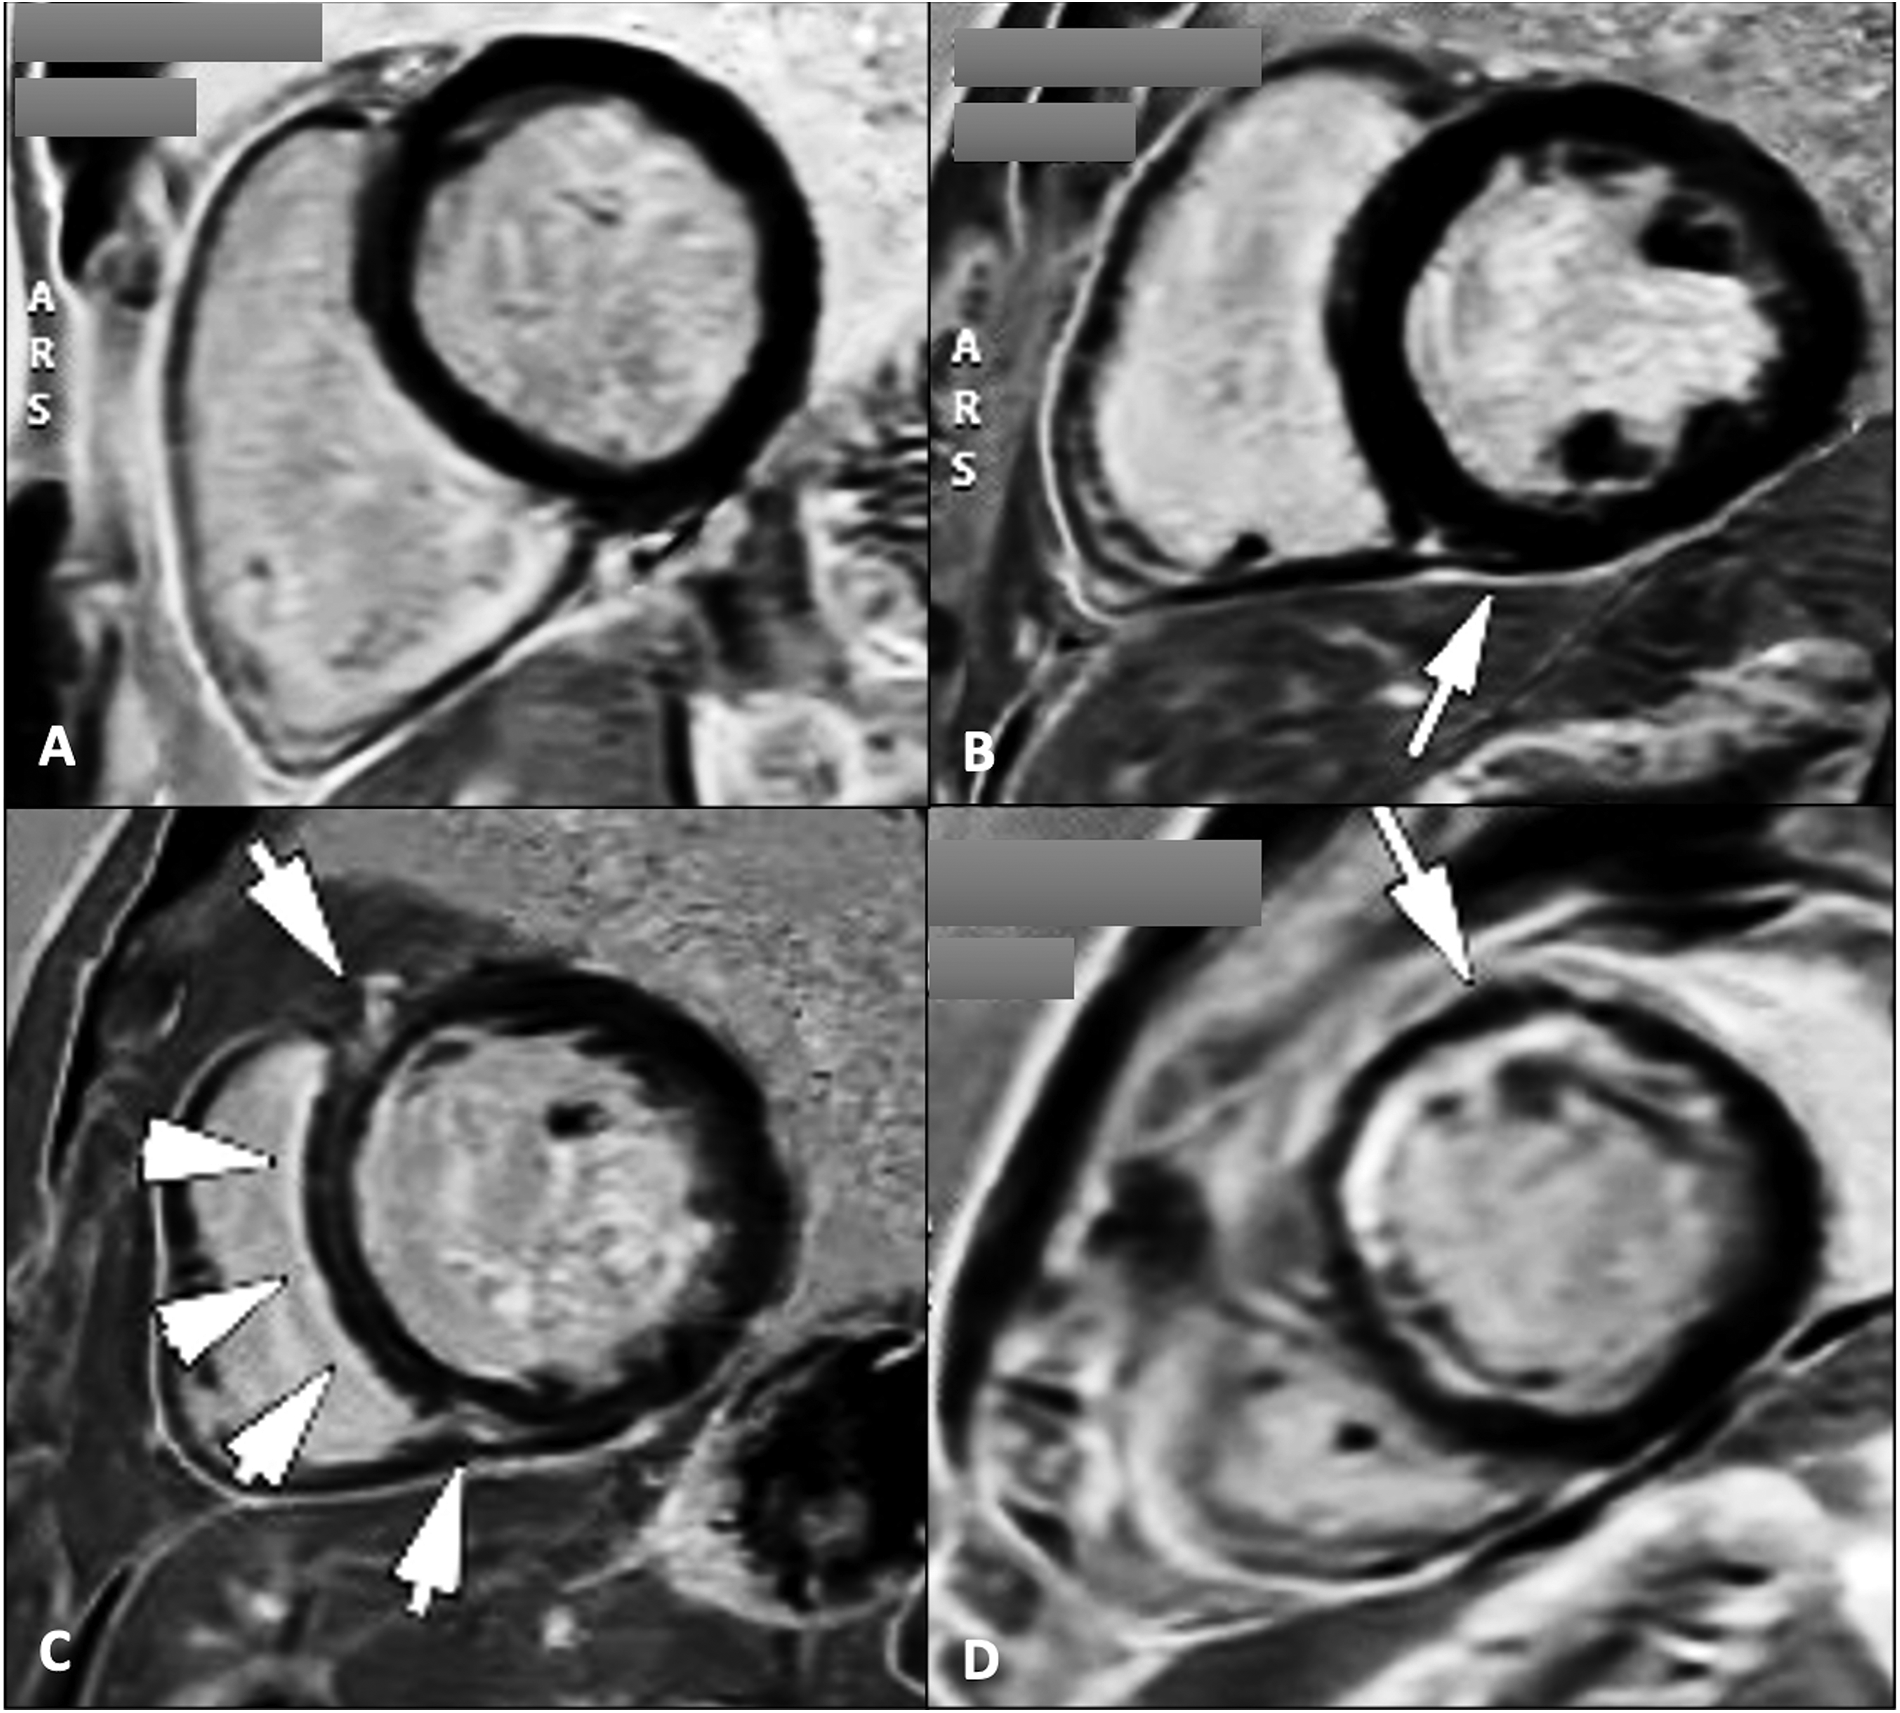

6.1 Tissue scar, myocardial viability and myocardial dyssynchrony evaluation

Evaluating the magnitude and location of the myocardial scar tissue by the use of late gadolinium enhancement (LGE) plays a crucial role (Figure 4), together with the evaluation of different LV contraction patterns (3). The identification and characterization of scar patterns is particularly valuable in predicting the clinical response in LBB pacing for CRT (98).

Figure 4

Cardiac magnetic resonance late gadolinium enhancement sequences for the assessment of myocardial scar tissue/fibrosis in four patients with dilated cardiomyopathy showing absence of LGE (A); localized LGE at the level of the inferior intraventricular septum on the RV insertion point (B); midwall linear fibrosis at the level of the intraventricular septum commonly known as “septal stripe” LGE, and at the level of the RV insertion points (C); and subendocardial antero-septal and anterior wall LGE (D) types B and C LGE pattern are typically found in patients with genetic/idiopathic etiologies of dilated cardiomyopathies, while pattern D suggests an ischaemic etiology. LGE, late gadolinium enhancement; RV, right ventricle.

In patients with nonischemic dilated cardiomyopathy, significant myocardial fibrosis and reduced circumferential dyssynchrony at CMR were independently associated with unfavorable response and long-term events after CRT (99). On the other hand, in patients with ischemic cardiomyopathy, the size and position of the myocardial scar tissue significantly affect the response to CRT in two primary ways. Firstly, placing the LV pacing lead in scarred regions correlates with less clinical and echocardiographic improvements. Secondly, greater scar burden corresponds to reduced residual LV contractility (74). A substantial scar extent (>33%) or high transmurality (>51%) serve as unfavorable predictors for CRT response. Interestingly, lateral wall scarring was less predictive of CRT response than septal scarring. The presence of septal LGE, whether ischemic or non-ischemic, is a robust indicator for predicting non-response and unfavorable long-term outcomes after CRT (77, 100).

This can be explained by the reduction in the typical LBBB -induced septal motion pattern (101) due to the decreased contractility of the lateral wall. The septum is thereby less stretched and SF and ApRock are diminished (102). Recent studies suggest that septal scar evaluation by CMR LGE together with SF visual assessment by CMR cine sequences as a singular imaging modality, together with other parameters such as delayed aortic valve opening measured relative to both end-diastole, and to pulmonic valve opening, or changes in septal-to-LV free-wall curvature ratios provide further insights into mechanical dyssynchrony, and accurately identify responders to CRT, while also reliably predicting long-term survival (103). If septal LGE is absent, the response rate remains outstanding, regardless of the presence or absence of other parameters of dyssynchrony. Conversely, if septal LGE is present without the occurrence of SF, the likelihood of a favorable response to CRT is significantly diminished, and if both septal LGE and SF are present, patients could respond positively to CRT (69).